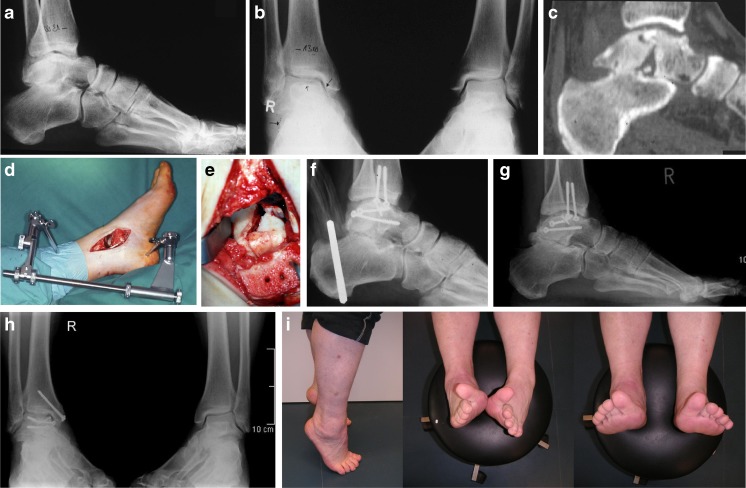

Fig. 3.

a,b Type III calcaneal malunion with severe loss of height after nonoperative treatment. c,d Subtalar distraction bone block arthrodesis leads to a restoration of height with correction of the talus-first metatarsal axis in the lateral radiographs